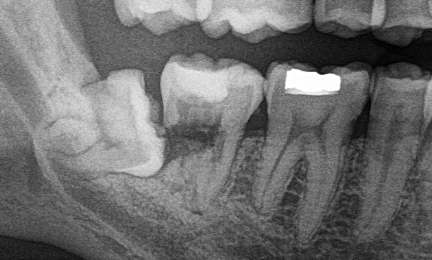

A fogászati szárnyas röntgen (Bite-wing) alkalmas a fogak közötti vagy a tömések alatti fogszuvasodás feltárásában, amelyek szabad szemmel nem láthatóak.